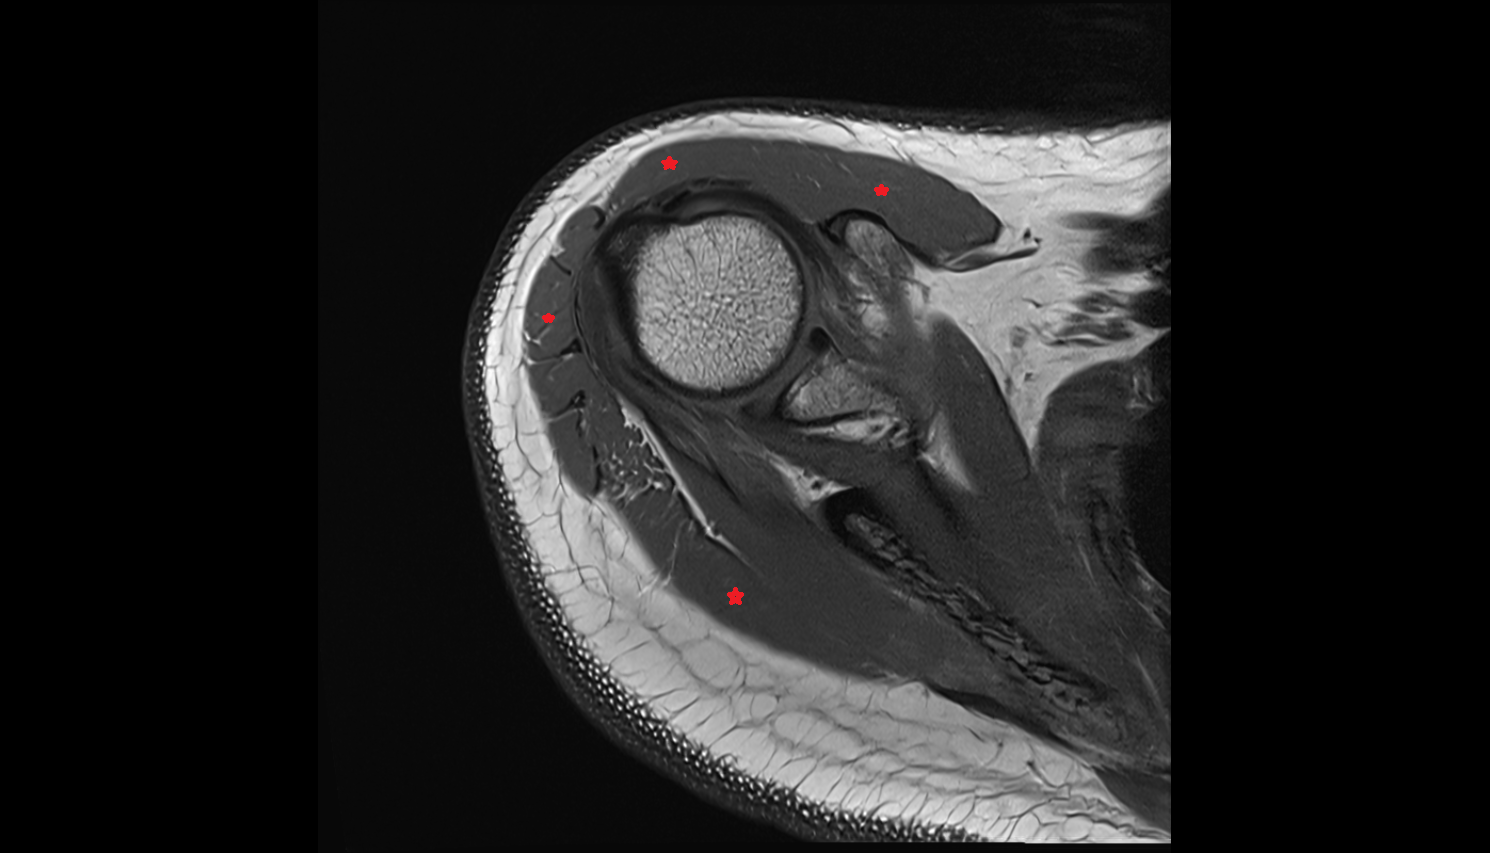

- Subscapularis tendon

- Supraspinatus tendon

- Glenohumeral ligaments

- Superior glenohumeral ligament

- Middle glenohumeral ligament

- Inferior glenohumeral ligament

- Glenohumeral joint capsule

- Glenoid labrum